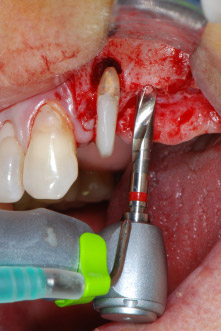

IImplant beds were prepared at sites 25 and 26 with rotary instruments, used in a contra-angle handpiece with a 20 : 1 transmission ratio with an updated powerful implant motor (Implantmed, W&H) (Fig. 8).

Due to its precise and gentle action, both the periodontal debridement and the apicoectomy at site 24 were carried out with a piezoelectric unit (Fig. 19). To avoid the risk of losing the tooth, thorough cleaning was necessary, but without exerting too much pressure. The device was also useful for debriding the bone at the surgical site, which works very well given the specific cavitation effect and cutting characteristics of the technology.

The implant bed was prepared with a new implant motor (Fig. 20), in combination with a contra-angle handpiece specifically designed for oral surgery and implantology.

The transmission rate of 20:1 together with the implant motor’s high torque of up to 6.2 Ncm allowed for slow speed preparation, implant insertion and thread cutting. Final preparation up to the sinus membrane was again performed with the piezoelectric unit and a round diamond instrument.